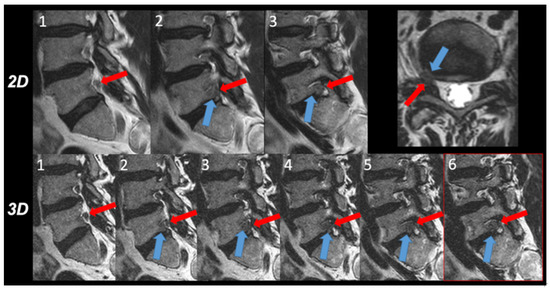

- 2D T2w TSE sequence: acquisition sagittal, repetition time (TR) 3000 ms, echo time (TE) 100 ms, flip angle 90°, echo train length 20, number of echoes 1, FOV 160 × 270 × 65 mm, slice thickness 4 mm, acquired voxel size 0.75 × 0.95 × 4.0 mm3, reconstructed voxel size: 0.63 × 0.63 × 4.0 mm3, number of signal averages (NSA) 2.0. Acquisition time 03 min 02 s.

- 3D T2w TSE sequence: acquisition sagittal, DRIVE pulse yes, TR 1300 ms, TE 95 ms, flip angle 90°, echo train length 50, number of echoes 1, field of view (FOV) 200 × 300 × 90 mm3, acquired voxel size 0.8 × 0.8 × 1.0 mm3, reconstructed voxel size 0.4 × 0.4 × 0.5 mm3, number of slices 180, acceleration: Compressed SENSE factor 7.0, NSA 1.0, acquisition time 04 min 46 s. This sequence was accelerated with the compressed SENSE acceleration technique that uses a variable density Poisson disk-sampling scheme followed by iterative reconstruction. A more detailed description of this acceleration technique can be found elsewhere [10,13]. The sequence was generally acquired in the sagittal plane of the section parallel to the spinal column. In patients with scoliosis, however, a secondary curved sagittal reconstruction parallel to the scoliotic lumbar vertebrae was obtained. Curved transverse reconstructions were computed parallel to the individual disc levels.